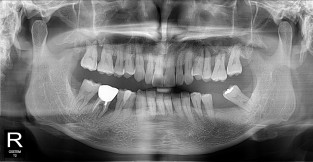

• 3

전체어금니

치료기간 : 2021-10-20 ~ 2023-08-31

1. 상기 x-ray 이미지 모두 동일한 해당 의료기관에서 진료한 환자입니다.

2. 상기 x-ray 이미지 모두 동일 인물의 것입니다.

3. 치료 전 이미지는 2021-10-20에 촬영했으며, 치료 후 이미지는 2023-08-31에 촬영하였습니다.

4. 상기 x-ray 이미지 모두 동일 조건에서 환자분의 동의를 받아촬영되었습니다.

* 임플란트 시술은 환자분의 상태(고혈압, 당뇨 등)에 따라 부작용이 있을 수 있으니, 반드시 전문의와 상담이 필요합니다.

* 임플란트 수술 부작용

: 수술 후 출혈, 교합, 통증, 붓기, 염증 등의 문제점이 발생할 수 있습니다.)